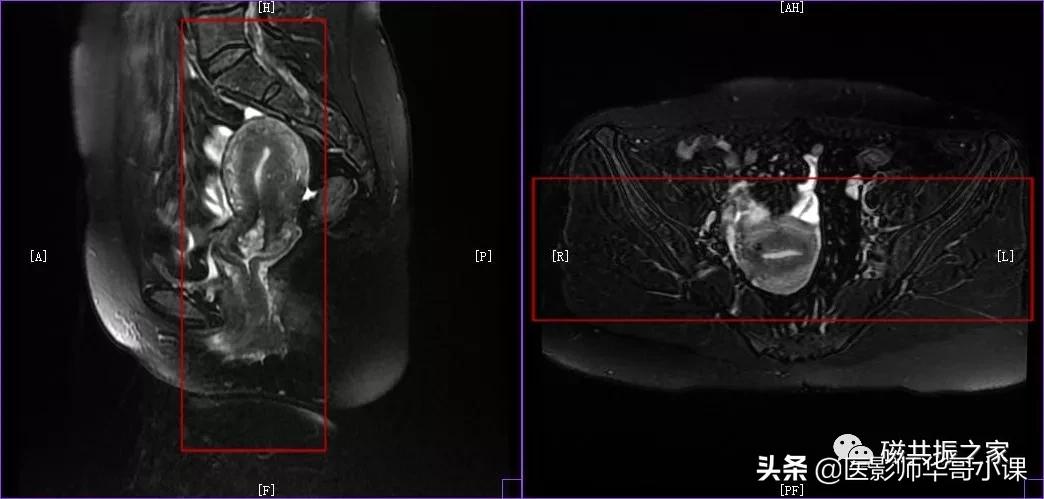

子宫MRI扫描前应先行1-2个大范围的 全盆腔 扫描序列,通常为大范围的T1WI和T2WI 压脂序列;在冠状位和矢状位上定位,按照常规的横轴位扫描即可。

行大范围扫描的目的:

1.了解盆腔内病变的大体情况。

2.观察盆腔内出血、转移、周围侵犯等情况。